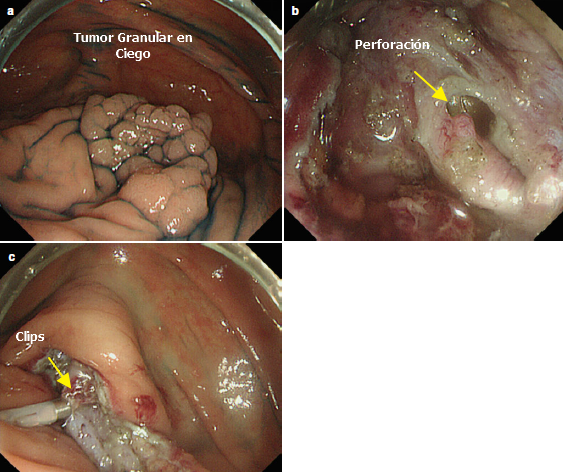

- Para la perforación durante la resección submucosa y mucosal en el tracto gastrointestinal los endoclips son la terapia de elección. Si el orificio es muy grande la aplicación de clips en los extremos puede reducir el diámetro y hacer más factible la aproximación de los bordes. Si esto falla un endoclip con endoloop puede ser efectivo.

- Existen 2 tipos de Clips: los que se colocan a través del endoscopio y los que se colocan sobre el endoscopio (OTSC). Los clips convencionales se utilizan en perforaciones pequeñas (menores a 1 centímetro). Los OTSC son efectivos en defectos menores de 2 centímetros.